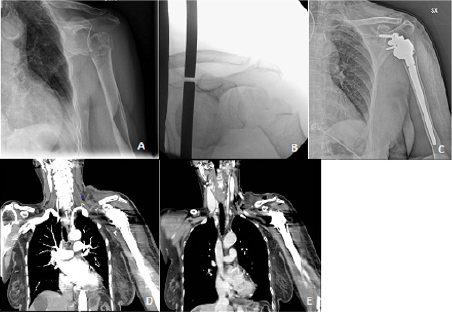

A 79-year-old patient accidentally fell at home tripping over her shoes. She got in our emergency department with pain and functional limitation at her left shoulder. The patient was conscious, oriented with no headache, no nausea, no vomiting, no apparent motor or sensory deficits and valid bilateral radial pulses. Hypertension, vascular encephalopathy, intestinal sub-occlusion, partial nephrectomy and chronic therapy with acetylsalicylic acid (ASA) and atenolol were part of patient’s medical history. Barthel index premorbid was 90/100. Standard radiographs of her left shoulder were performed revealing a displaced, fracture-anteriordislocation of the proximal left humerus, described as type 11 C-3 fracture according to the AO/OTA classification (Figure 1A-1B). After two unsuccessful attempts of closed reduction of the humeral head, a Desault bandage was applied.

The patient was then admitted to our Orthopedic department in order to be treated surgically, with a reverse total shoulder replacement. Pre-operative routine tests and anesthesia evaluation were performed. Surgery was performed under general anesthesia about 30 h after trauma, through a lateral trans-deltoid approach in a beach chair position. After appropriate fracture site exposing, antero-inferior dislocation of the humeral head was found, medially to the coracoid and in contact with the brachial plexus. The transdeltoid approach not enabling the humeral head to me removed easily, caused a greater medial dislocation of the bone fragment. After several attempts the humeral head was removed and a Lima SMR Reverse Shoulder Prosthesis (Villanova di San Daniele del Friuli, Udine) was implanted (Figure 1C). The duration of the operation was 2 hours ad no significant intraoperative blood loss was detected. At the end of the procedure, arm sling was positioned at 15° of abduction.

Signs of acute ischemia of the left upper limb and axillary nerve stupor were detected clinically approximately 2 hours after surgery. The Patient reported pain, paraesthesia and functional limitation of the wrist and fingers with absence of peripheral arterial pulses. Urgent vascular surgery evaluation was requested: the duplex-ultrasound revealed patency of the subclavian artery up to the distal third but absence of flow within the axillary, humeral, radial and ulnar arteries. A CT angiography of the left upper limb (Figure 1 D-E) confirmed occlusion of the axillary artery at the origin, without opacification of the downstream vessels. After 5 hours from the diagnosis of left upper limb ischemia and under general anaesthesia, vascular surgeons performed an angiography with percutaneous left femoral access. Due to lack of visualization of downstream vessels, occlusion of the first tract of the axillary artery was diagnosed (Figure 2A). Angioplasty and stenting of the left axillar artery restored blood flow to the downstream vessels though appearing to be diffusely thrombosed and demanding for an open surgery (Figure 2B).